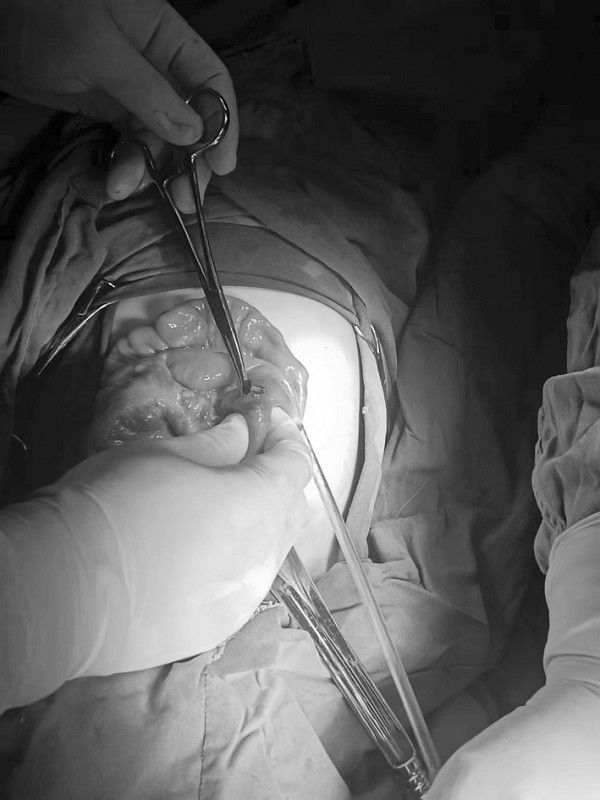

1.患儿:李某某,性别:男,年龄:2岁;简要病史:2岁男孩,因间断腹痛5天,发现消化道异物1天入院。5天前患儿无明显诱因出现腹痛,家长未予特殊重视,1天前患儿出现呕吐伴便秘,就诊于当地医院,行腹部X线片提示消化道异物(磁力球?),遂急诊就诊于我院,诊断“消化道异物(磁力球?)”收住我科。发病后患儿精神食欲差,予以开塞露后排大便1次,小便正常。既往身体健康,无家族遗传病史,心肺腹查体无异常。初步诊断:消化道异物(磁力球?)接下来,患儿需要做什么检查呢?是继续观察自行排出?还是内镜下取出?又或是剖腹探查取出呢?完善腹部X片 (两次间隔时间6小时)显示:磁力球位置未见明显变化(如下图),拟行手术治疗,手术方式为:剖腹探查术。手术探查示 (如下图):胃大弯处可见有2处直径约0.5cm穿孔 (穿孔内取出磁力球5颗),距屈氏韧带约40cm肠管近系膜侧可见2处直径约0.5cm穿孔 (穿孔内取出磁力球10颗),抗菌薇乔全层间断缝合一层胃大弯及小肠肠管穿孔,间断浆肌层加固一层;查无漏气漏液现象,吻合口直径通过顺畅。术毕。术后治疗:予以抗感染、肠外营养、过渡饮食对症治疗,患儿恢复顺利,康复出院。2.患儿:贾某某,性别:男,年龄:1岁10个月;简要病史:1岁10个月男孩,因精神反应欠佳伴烦躁哭闹4天入院。患儿于入院近4天精神反应欠佳,烦躁、哭闹,手捂腹部,呕吐2次,就诊于卫生所予以腹部外敷药物治疗,效果欠佳,后就诊于妇幼保健院,行腹部X片检查,提示消化道异物,自发病以来精神可,食欲欠佳,大便1次,小便量少。既往身体健康,无家族遗传病史,心肺腹查体无异常。初步诊断:消化道异物(磁力球?)完善腹部X片(两次间隔时间6小时)显示:磁力球位置未见明显变化(如下图),拟行手术治疗,手术方式为:剖腹探查术。手术探查示(如下图):距屈氏韧带约30cm小肠有2处直径约0.5cm穿孔(穿孔内取出磁力球1颗、螺丝1颗),距肛门口20cm处乙状结肠近系膜侧可见2处直径约0.5cm穿孔 (穿孔内取出磁力球9颗),据回盲部40cm处小肠系膜可见2处直径约0.5cm穿孔。术后治疗:予以抗感染、肠外营养、过渡饮食对症治疗,患儿恢复顺利,康复出院。